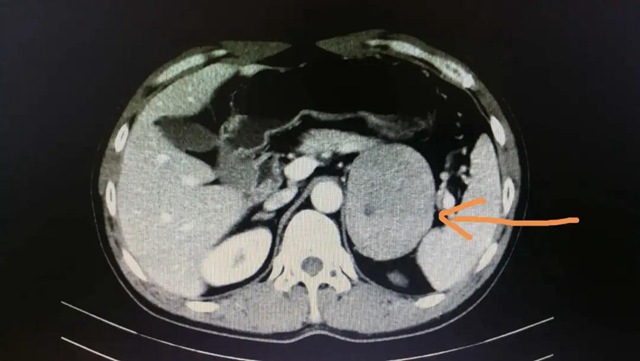

該患者,男性,52歲,因“尿頻2年”住院,檢查發(fā)現(xiàn)左側(cè)腎上腺腫瘤(9cm)。

▲CT掃描下的腎上腺腫瘤